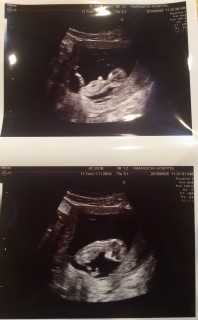

今回から腹部エコーになりました。かなり分かりにくいですが、左が頭で右が体です。 背骨や足の骨も確認でき、背中のうしろもキレイだと言われてホッとしました。 お尻や手を動かして元気に動いてくれていました♪(*^▽^)v 頭の大きさ:2.3cm

頭からお尻までの大きさが6㎝で、頭が2㎝でした。 お顔も見せてもらいました。 小さな手が動いているのがとっても可愛らしかったです。

6.25cmになりました~! 首の後ろのむくみもなく、順調に育っているようです。鼻の骨も出来て、目も出来てました。 旦那サマも一緒に妊婦検診に参加し、動く赤ちゃんを初めて見ました。感動してくれたようで良かった♪

1ヶ月振りの健診。つわりもあまりなく、ちゃんと育っているか不安はあったけどエコーを見て安心。流産の兆候もなく元気に育っているそう!手足も動かしてて感動…っ!CRLは64.9mmでしたー!次も1ヶ月後の健診なので、どれくらい成長しているか楽しみ~